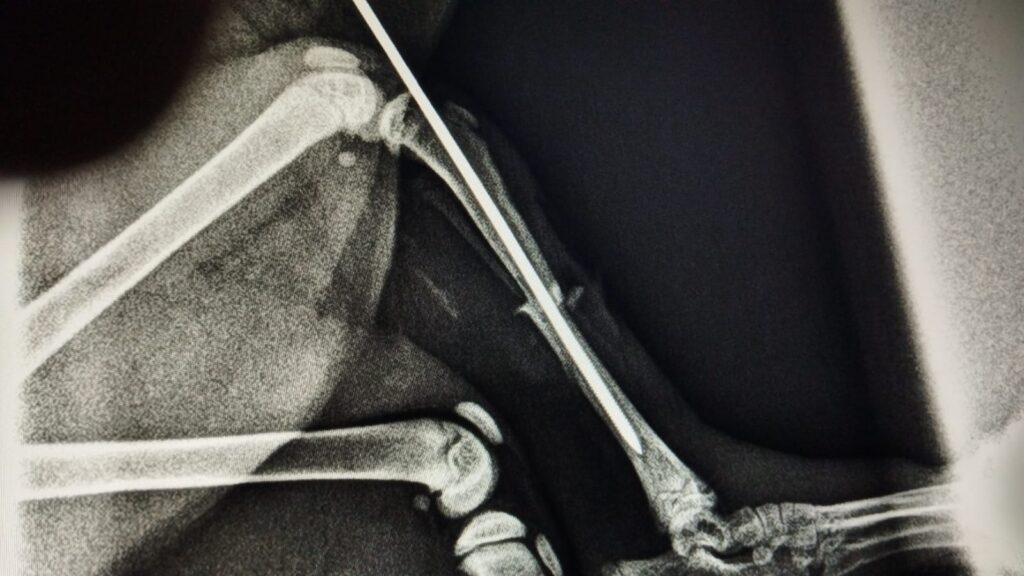

Pili konnte ihre Hinterbeine nicht bewegen, ihre Schließmuskeln funktionierten nicht, sie hatte eine gebrochene Hüfte, aber sie hatte großen Lebenswillen und dank der Pflege ihres Betreuers gewann sie nach und nach ihre Mobilität zurück.

Sie wollte sich so sehr bewegen und Spaß haben, dass wir glauben, dass sie von einer Höhe wie einem Sofa oder Bett gefallen ist und dabei so viel Pech hatte, dass sie sich dabei ihr Beinchen gebrochen hat. Sie wurde notoperiert und erholte sich schnell und gut, ohne bleibende Schäden.

Nach wenigen Wochen litt sie unter einer Stuhlverstopfung, weshalb sie erneut operiert werden musste, um den Stuhl aus dem Darm zu entfernen. Pili muss ballaststoffreiche Nahrung und Abführmittel zu sich nehmen, damit dies nicht erneut auftritt, da ihre Hüfte den Analkanal verengt, weshalb wir auf ihre Ernährung achten müssen.